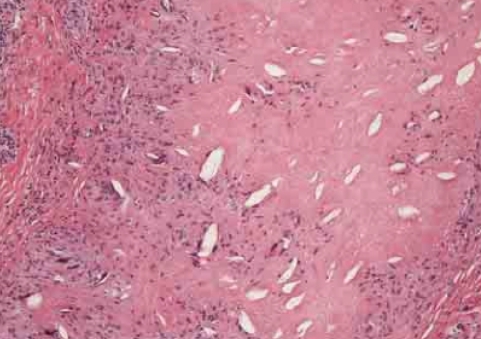

또한, 결절은 스컬트라의 구성 성분인 PLLA(Poly L lactic acid) 성분만 뭉치는게 아니라 'PLLA가루 + 거대다핵세포' 형태로 형성되는데요.

위에 보이는 것처럼 스컬트라 결절이 발생하면 단단한 거대다핵세포들이 피부 속에 분포되어 있는 것을 볼 수 있죠.